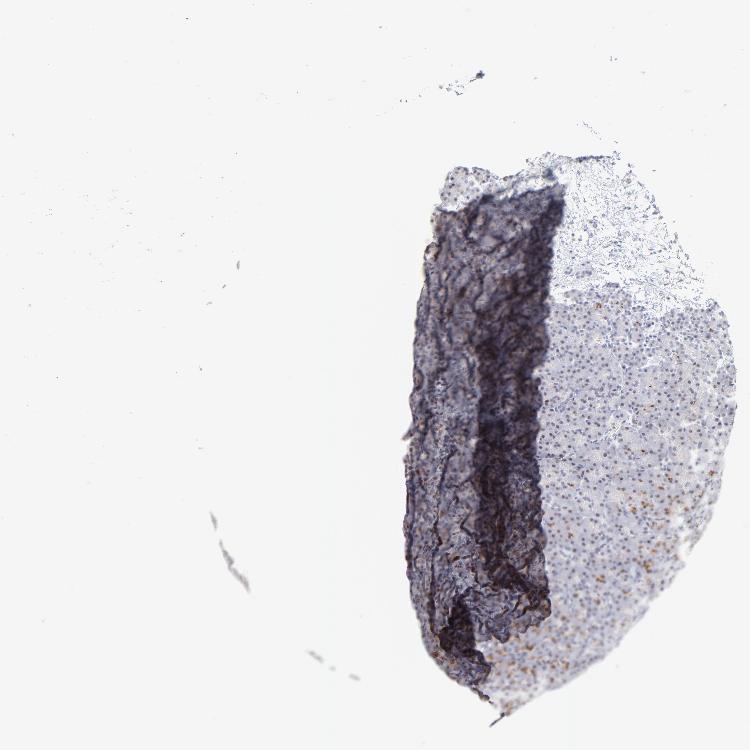

TISSUE PRIMARY DATA PANCREAS Show tissue menu

PANCREAS - Antibody stainingi

Antibody staining in the annotated cell types in the current human tissue is reported as not detected, low, medium, or high, based on conventional immunohistochemistry profiling in selected tissues. This score is based on the combination of the staining intensity and fraction of stained cells.

Each image is clickable and will lead to virtual microscopy that enables deeper exploration of all samples and also displays staining intensity scores, fraction scores and subcellular localization as well as patient and tissue information for each sample.

Antibody HPA045168Antibody CAB000147Antibody CAB003839Antibody CAB003840Antibody CAB075726Antibody CAB075727

Exocrine glandular cells HighNot detectedMediumMediumHighHigh

Pancreatic endocrine cells HighNot detectedNot detectedMediumHighMedium